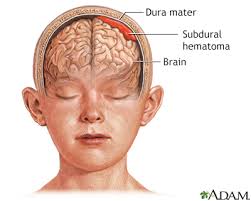

Notice how the brain is enclosed in the skull. Because the skull, obviously, can’t expand, the pressure on the brain can lead to neural death faster than anticipated